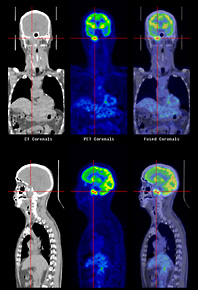

「PET(陽電子放射断層撮影)」はがんの検査法の1つです。がん細胞が正常細胞の3~8倍ものブドウ糖を取り込むという特性を利用して、ブドウ糖に似せた薬剤を体内に注射し、薬剤ががん細胞に集まるところを画像化します。がんを確実に診断するために、これらの診断を複数組み合わせて行う場合もあります。

CT画像(左上下)、PET画像(中央上下)とこれらの合成画像(右上下)。(画像提供:厚地記念クリニックPET画像診断センター)